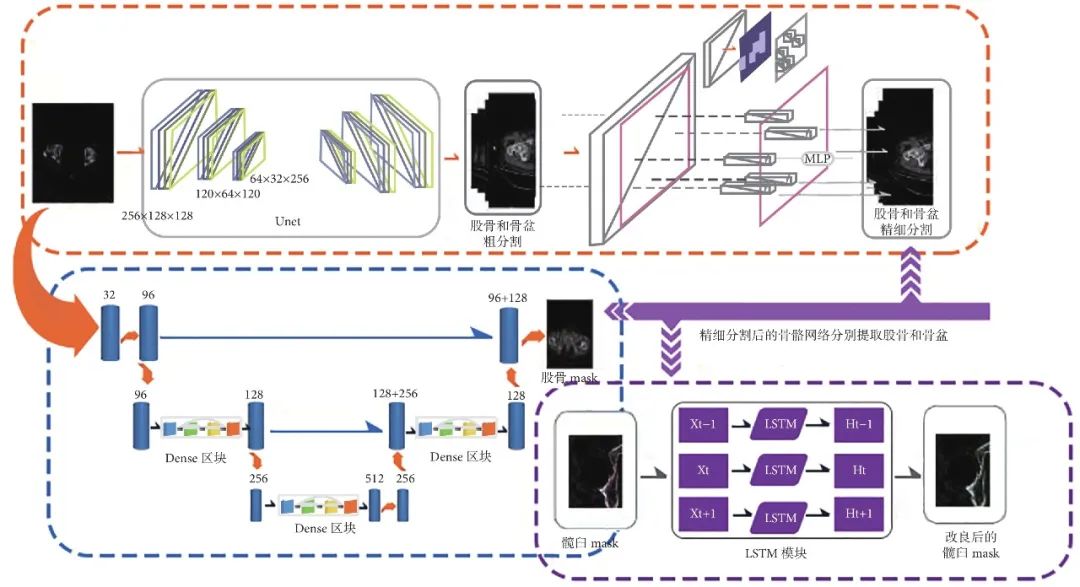

1.2.1 智能规划髋臼侧 AIHIP 系统采用独创的G-NET 神经网络技术(图 2),通过融合 Unet 结构、DenseBlock 结构、LSTM 网络和 PointRend 技术,可以精准识别骨骼边缘并进行精确分割(图3a)。接着在骨盆分割基础上对髋臼进行拟合,进而计算髋臼的旋转中心以及半径;再结合骨盆矫正结果(图 3b、c),规划出髋臼杯合适位置(图3d~h)。

1.2.2 智能规划股骨侧 根据测得的股骨髓腔直径并结合 S-ROM 柄特征,确定股骨颈截骨位置与保留股骨距长度(图 3i),匹配适当型号、内外翻角度、放置位置的股骨柄(图 3j~l),根据双下肢长度差绝对值智能匹配适当球头。此外,AIPHIP 软件可根据前期识别的解剖标志点变化情况,模拟术前(三维重建后坐标与二维横断面、矢状面、冠状面三轴联动,点击其中 1 个视图,其他视图也会相应变化,图 3m)、术后效果(图 3n~p),测算股骨柄假体安放后双下肢长度差绝对值。

图 3 左髋 DDH 术前 AIHIP 软件设计 a. 骨盆分割;b. 骨盆矫正;c. 骨盆矫正透明图;d. 左侧髋臼杯安放 AI 术前规划;e~h. 左侧髋臼杯设计细节;i. 左侧髋臼杯安放横断位 AI 术前规划;j. 股骨截骨位置;k. 左侧股骨假体二维横断位规划;l. 左侧股骨假体二维矢状位规划;m. 术前 CT 与三维重建联动;n. 模拟术后第 1 天 X 线片;o. 模拟术后第 1 天正视透明图;p. 模拟术后第 1 天侧视透明图